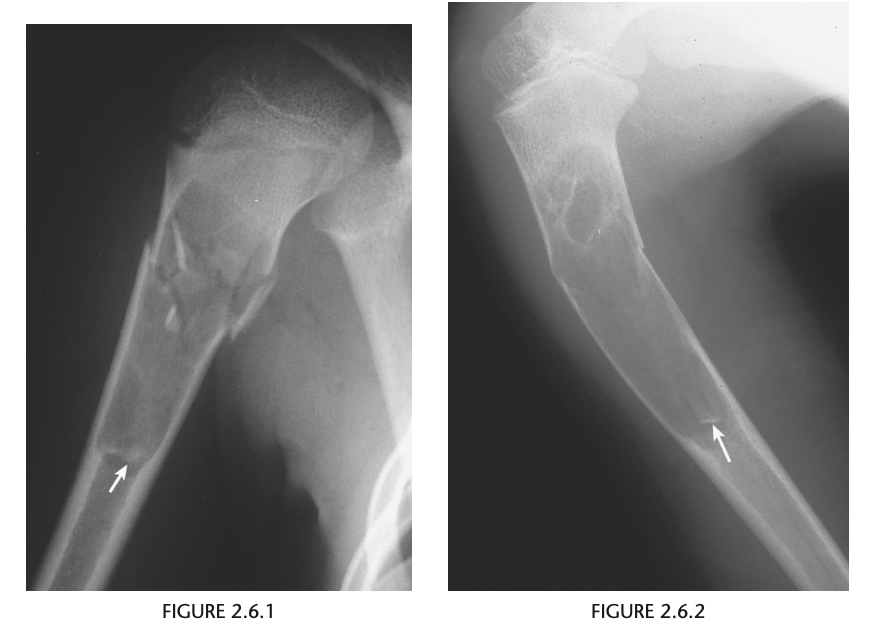

11 year old boy with right arm pain after fall

AP & Lateral views of the proximal right humerus well-circumscribed, geographic, lytic me-

taphyseal lesion with cortical thinning. The lesion

has well-defined margins and no demonstrable ma-

trix. A comminuted fracture has occurred, and frag-

ments of the cortex have fallen to the dependent

portion of the lesion (arrows)

Diagnosis: Unicameral bone cyst

“fallen-fragment sign” is the distinguishing

feature in these lesions because the fragments can

reach this position only in purely cystic lesions.

Lesions near the metaphysis are active, but as the

patient grows, the lesion migrates to the diaphy-

sis of the bone and becomes inactive. Treatment

includes curettage and packing with bone chips

or steroid injection.